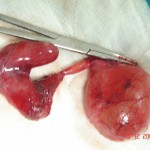

Acute Scrotum (Right scrotal Abscess)

Torsion of Left Undescended Testis (Pre operative and Operative Photo)

Acute Scrotum

Torsion Testis (Pre and Per operative photo)